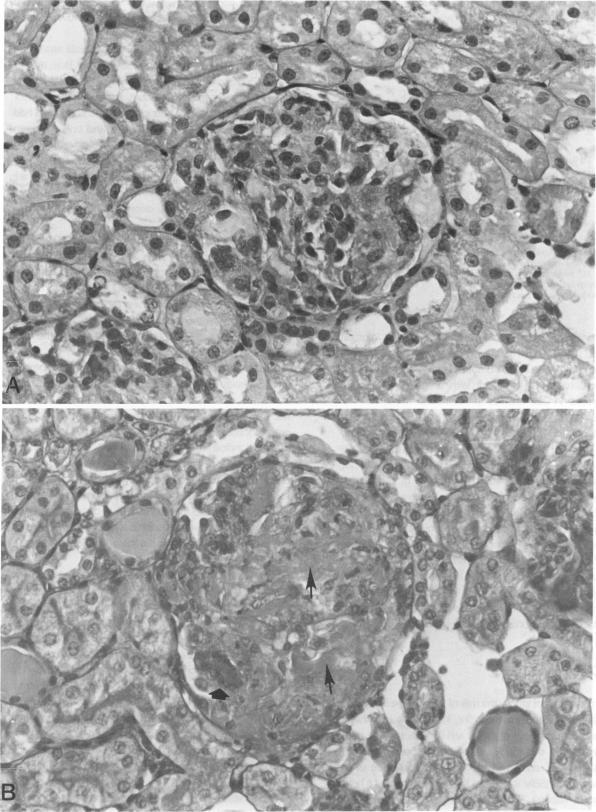

The terminal complement pathway (C5b to C9) has been demonstrated to have an important role in the mediation of glomerular immune injury in various models of experimental glomerulonephritis. In the present studies, the role of the terminal complement pathway in the accelerated autologous phase of anti-glomerular basement membrane (GBM) nephritis in the rabbit was investigated. Normocomplementemic rabbits and rabbits deficient in C6 (C6D) who are therefore unable to form the terminal complement pathway were immunized with sheep immunoglobulin G (IgG) before being injected with a subnephrotoxic dose of the gamma 2 fraction of sheep anti-rabbit GBM. C6D animals had a delay in the onset of the glomerular injury, as manifested by proteinuria. At 72 hours, controls had a greater degree of proteinuria (15.2 +/- 8.8 mg protein/mg creatinine vs. 2.6 +/- 2.1, P = 0.197), but at 120 hours there were no differences in proteinuria between C6D and control animals (11.1 +/- 3.6 mg protein/mg creatinine vs. 12.2 +/- 6.2, P = 0.89). Light microscopy demonstrated more severe glomerular injury in C6D animals with marked cellular proliferation and large areas of glomerular necrosis. Interestingly, C6D animals had significantly higher levels of sheep IgG remaining in their glomeruli at 120 hours (0.95 +/- 0.12 micrograms sheep IgG/1 x 10(4) glomeruli, N = 11, vs. 0.57 +/- 0.07, N = 11, P = 0.014) and 72 hours (1.22 +/- 0.25 micrograms, N = 3, vs. 0.60 +/- 0.15, N = 3, P = 0.104) compared with 24 hours when there was no difference (1.25 +/- 0.22 micrograms, N = 7, vs. 1.08 +/- 0.14, N = 7, P = 0.53). C6D rabbits had a greater rise in serum creatinine at 120 hours (2.3 +/- 0.5 mg/dl vs. 1.3 +/- 6.4, P = 0.132). We conclude that in C6D animals, the persistence of glomerular immune deposits is responsible for more severe renal injury and renal failure.

终末补体途径(C5b至C9)已被证明在多种实验性肾小球肾炎模型的肾小球免疫损伤介导中起重要作用。在本研究中,研究了终末补体途径在兔抗肾小球基底膜(GBM)肾炎加速自体期的作用。正常补体水平的兔和缺乏C6(C6D)因而无法形成终末补体途径的兔,在注射亚肾毒性剂量的羊抗兔GBM的γ2组分之前,先用羊免疫球蛋白G(IgG)进行免疫。C6D动物的肾小球损伤发病延迟,表现为蛋白尿。在72小时时,对照组的蛋白尿程度更高(15.2±8.8mg蛋白/ mg肌酐,而C6D组为2.6±2.1,P = 0.197),但在120小时时,C6D组和对照组动物的蛋白尿无差异(11.1±3.6mg蛋白/ mg肌酐,而对照组为12.2±6.2,P = 0.89)。光镜检查显示C6D动物的肾小球损伤更严重,有明显的细胞增殖和大面积的肾小球坏死。有趣的是,C6D动物在120小时(0.95±0.12μg羊IgG / 1 x 10(4)个肾小球,N = 11,而对照组为0.57±0.07,N = 11,P = 0.014)和72小时(1.22±0.25μg,N = 3,而对照组为0.60±0.15,N = 3,P = 0.104)时肾小球中残留的羊IgG水平明显高于24小时时(1.25±0.22μg,N = 7,而对照组为1.08±0.14,N = 7,P = 0.53),此时无差异。C6D兔在120小时时血清肌酐升高幅度更大(2.3±0.5mg / dl,而对照组为1.3±6.4,P = 0.132)。我们得出结论,在C6D动物中,肾小球免疫沉积物的持续存在是导致更严重肾损伤和肾衰竭的原因。